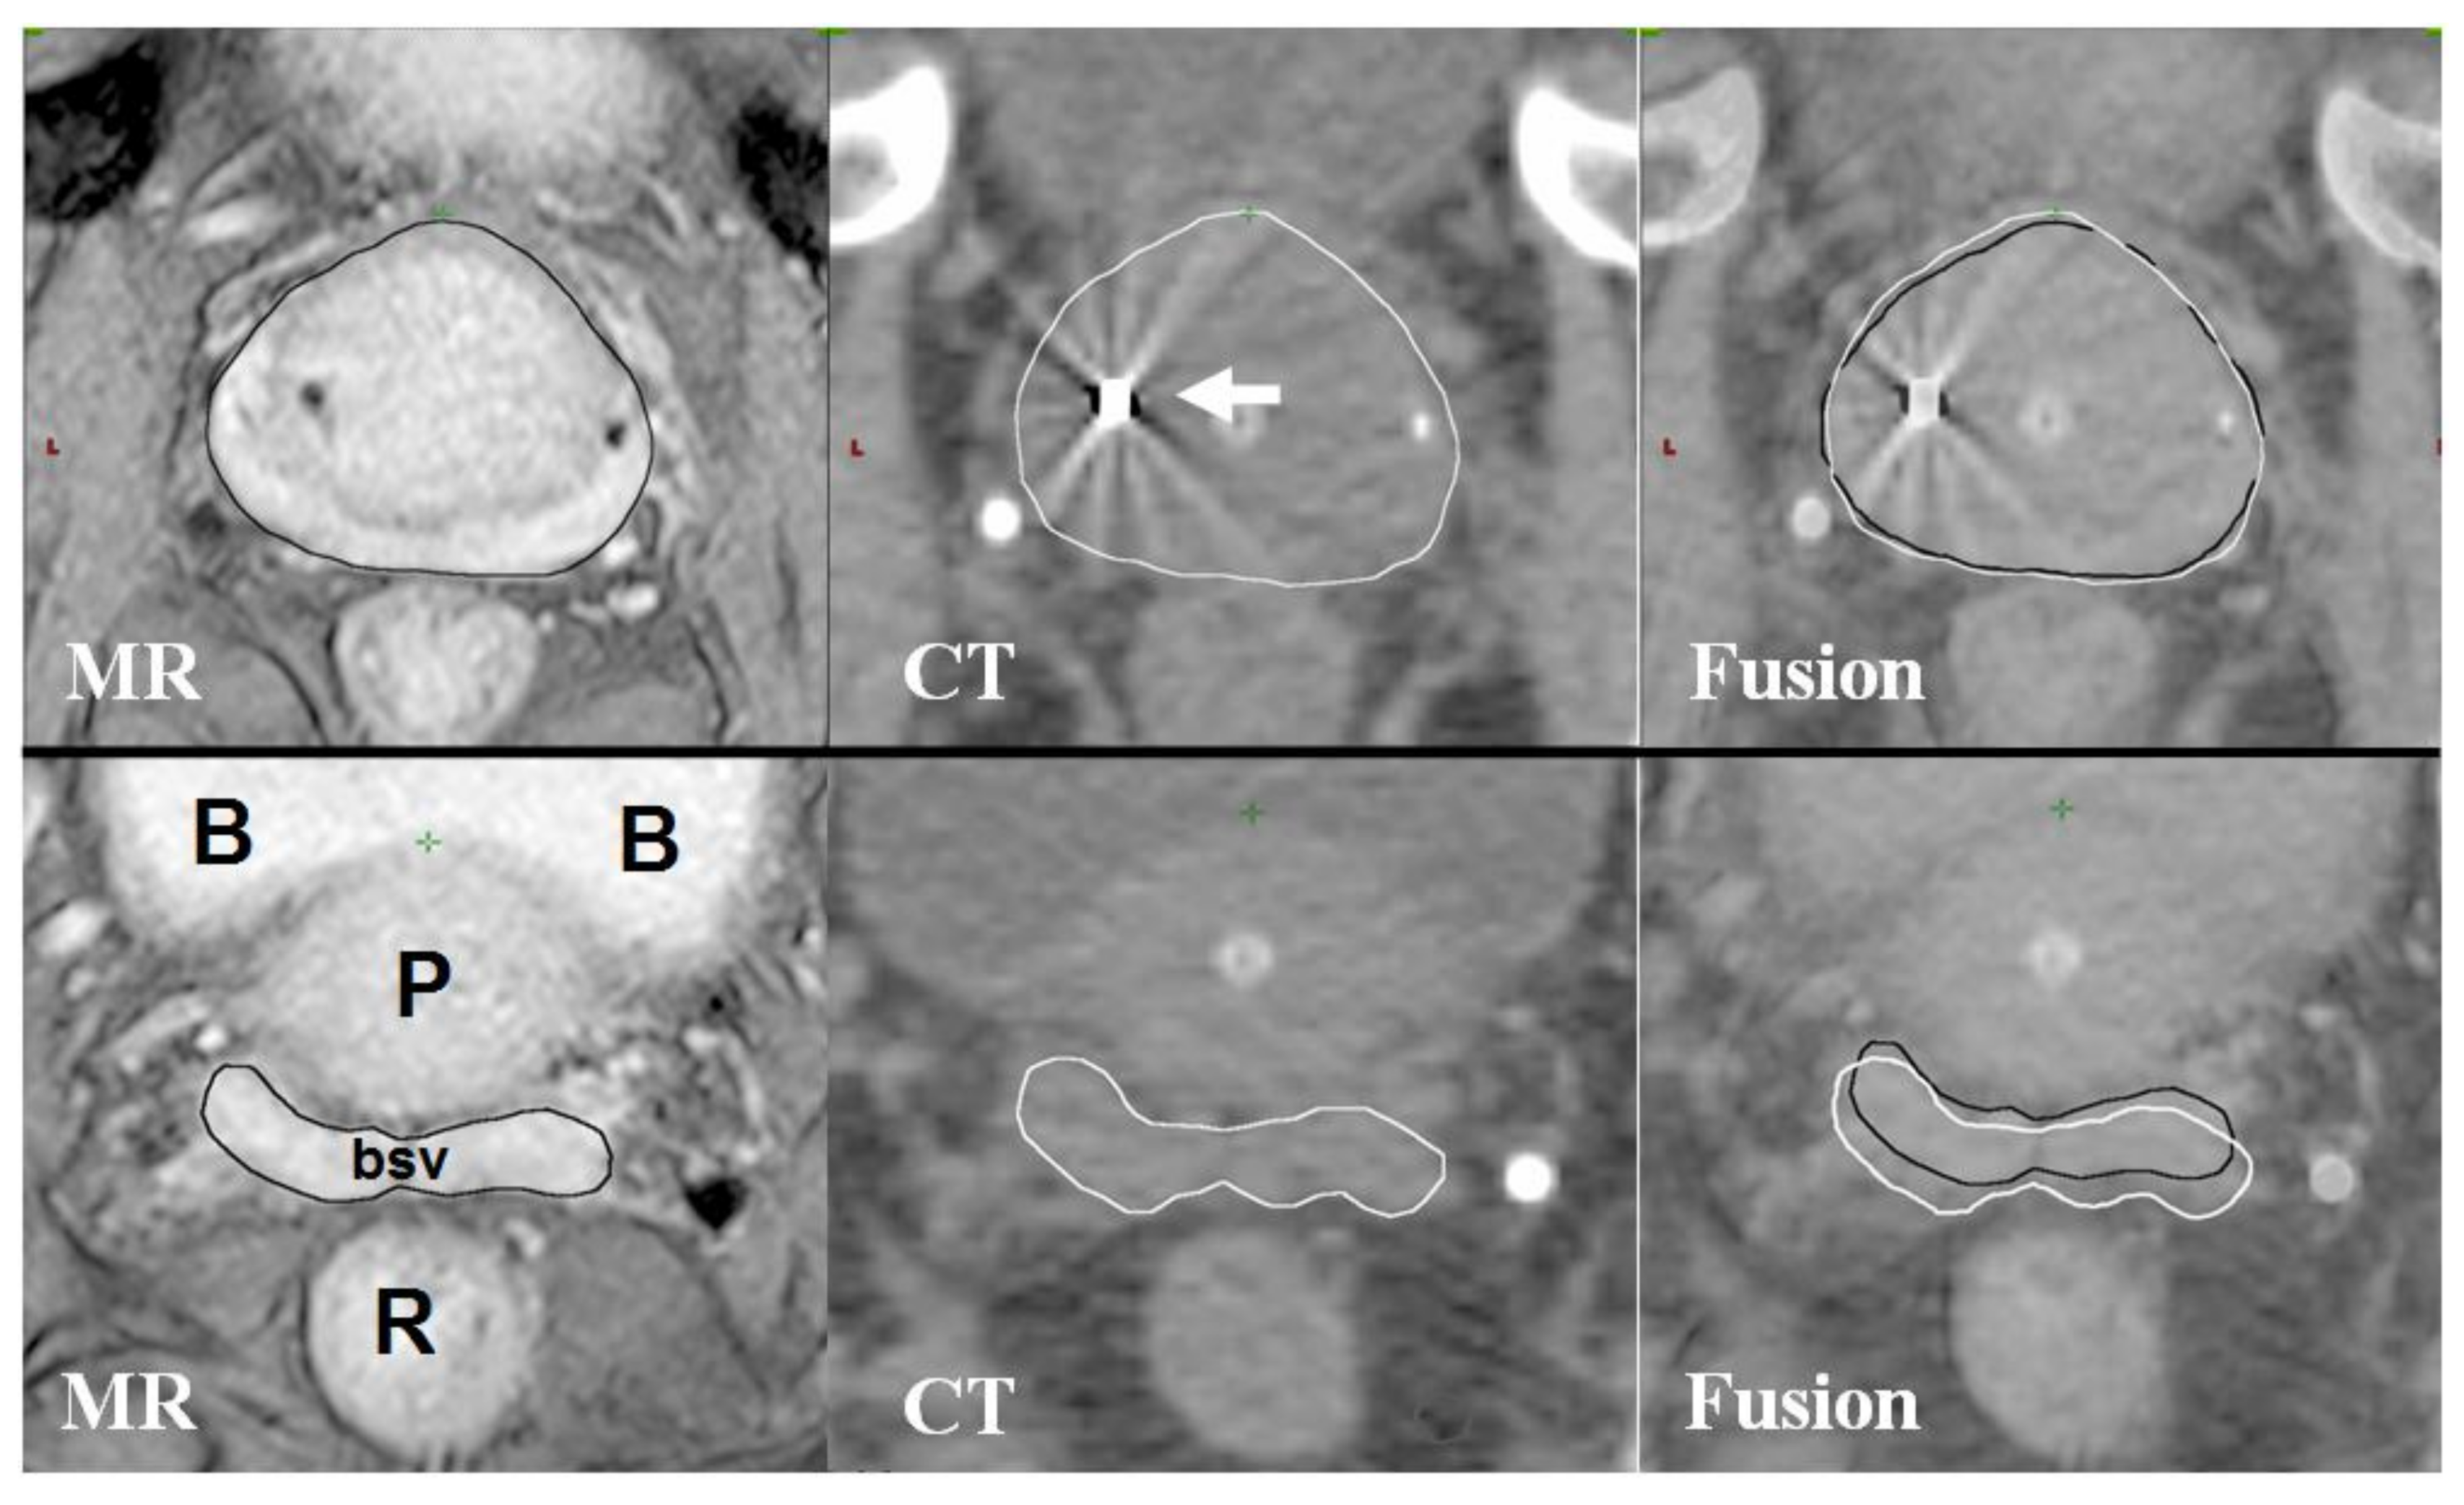

- Hentschel, B.; Oehler, W.; Strauss, D.; Ulrich, A.; Malich, A. Definition of the ctv prostate in ct and mri by using ct-mri image fusion in imrt planning for prostate cancer. Strahlenther. Onkol. 2011, 187, 183–190. [Google Scholar] [CrossRef] [PubMed]

- Debois, M.; Oyen, R.; Maes, F.; Verswijvel, G.; Gatti, G.; Bosmans, H.; Feron, M.; Bellon, E.; Kutcher, G.; Van Poppel, H.; et al. The contribution of magnetic resonance imaging to the three-dimensional treatment planning of localized prostate cancer. Int. J. Radiat. Oncol. Biol. Phys. 1999, 45, 857–865. [Google Scholar] [CrossRef]

- Steenbakkers, R.J.; Deurloo, K.E.; Nowak, P.J.; Lebesque, J.V.; van Herk, M.; Rasch, C.R. Reduction of dose delivered to the rectum and bulb of the penis using mri delineation for radiotherapy of the prostate. Int. J. Radiat. Oncol. Biol. Phys. 2003, 57, 1269–1279. [Google Scholar] [CrossRef]

- Sannazzari, G.L.; Ragona, R.; Ruo Redda, M.G.; Giglioli, F.R.; Isolato, G.; Guarneri, A. Ct-mri image fusion for delineation of volumes in three-dimensional conformal radiation therapy in the treatment of localized prostate cancer. Br. J. Radiol. 2002, 75, 603–607. [Google Scholar] [CrossRef] [PubMed]

- Amdur, R.J.; Gladstone, D.; Leopold, K.A.; Harris, R.D. Prostate seed implant quality assessment using mr and ct image fusion. Int. J. Radiat. Oncol. Biol. Phys. 1999, 43, 67–72. [Google Scholar] [CrossRef]

- Kagawa, K.; Lee, W.R.; Schultheiss, T.E.; Hunt, M.A.; Shaer, A.H.; Hanks, G.E. Initial clinical assessment of ct-mri image fusion software in localization of the prostate for 3D conformal radiation therapy. Int. J. Radiat. Oncol. Biol. Phys. 1997, 38, 319–325. [Google Scholar] [CrossRef]

- Parker, C.C.; Damyanovich, A.; Haycocks, T.; Haider, M.; Bayley, A.; Catton, C.N. Magnetic resonance imaging in the radiation treatment planning of localized prostate cancer using intra-prostatic fiducial markers for computed tomography co-registration. Radiother. Oncol. 2003, 66, 217–224. [Google Scholar] [CrossRef]